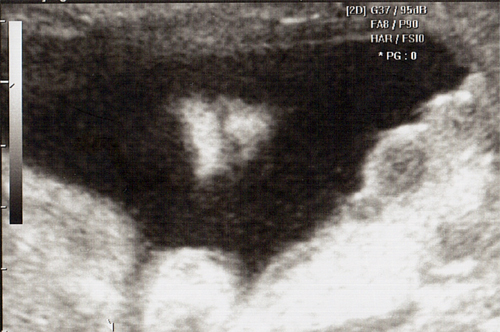

강아 ^^ 21주 강이의 정밀 초음파를 봤어 일반 초음파 보다는 더 정밀하게 나오더라구 엄청 커버린 강이가 한눈에 보이지 않을정도로 이제는 초음파 기계가 작아 보이더라..

강이 얼굴을 딱~ 보는순간.. 심장이 멈추고 코를 보는순가 다시 심장이 뛰기 시작했어 딱.. 아빠 코를 닮았더라 ^^:.. 이쁜자식...

다음에 가면 입체 초음파를 볼꺼야 더더욱 아빠를 닮은 강이를 볼수 있겠지 기대가 된다